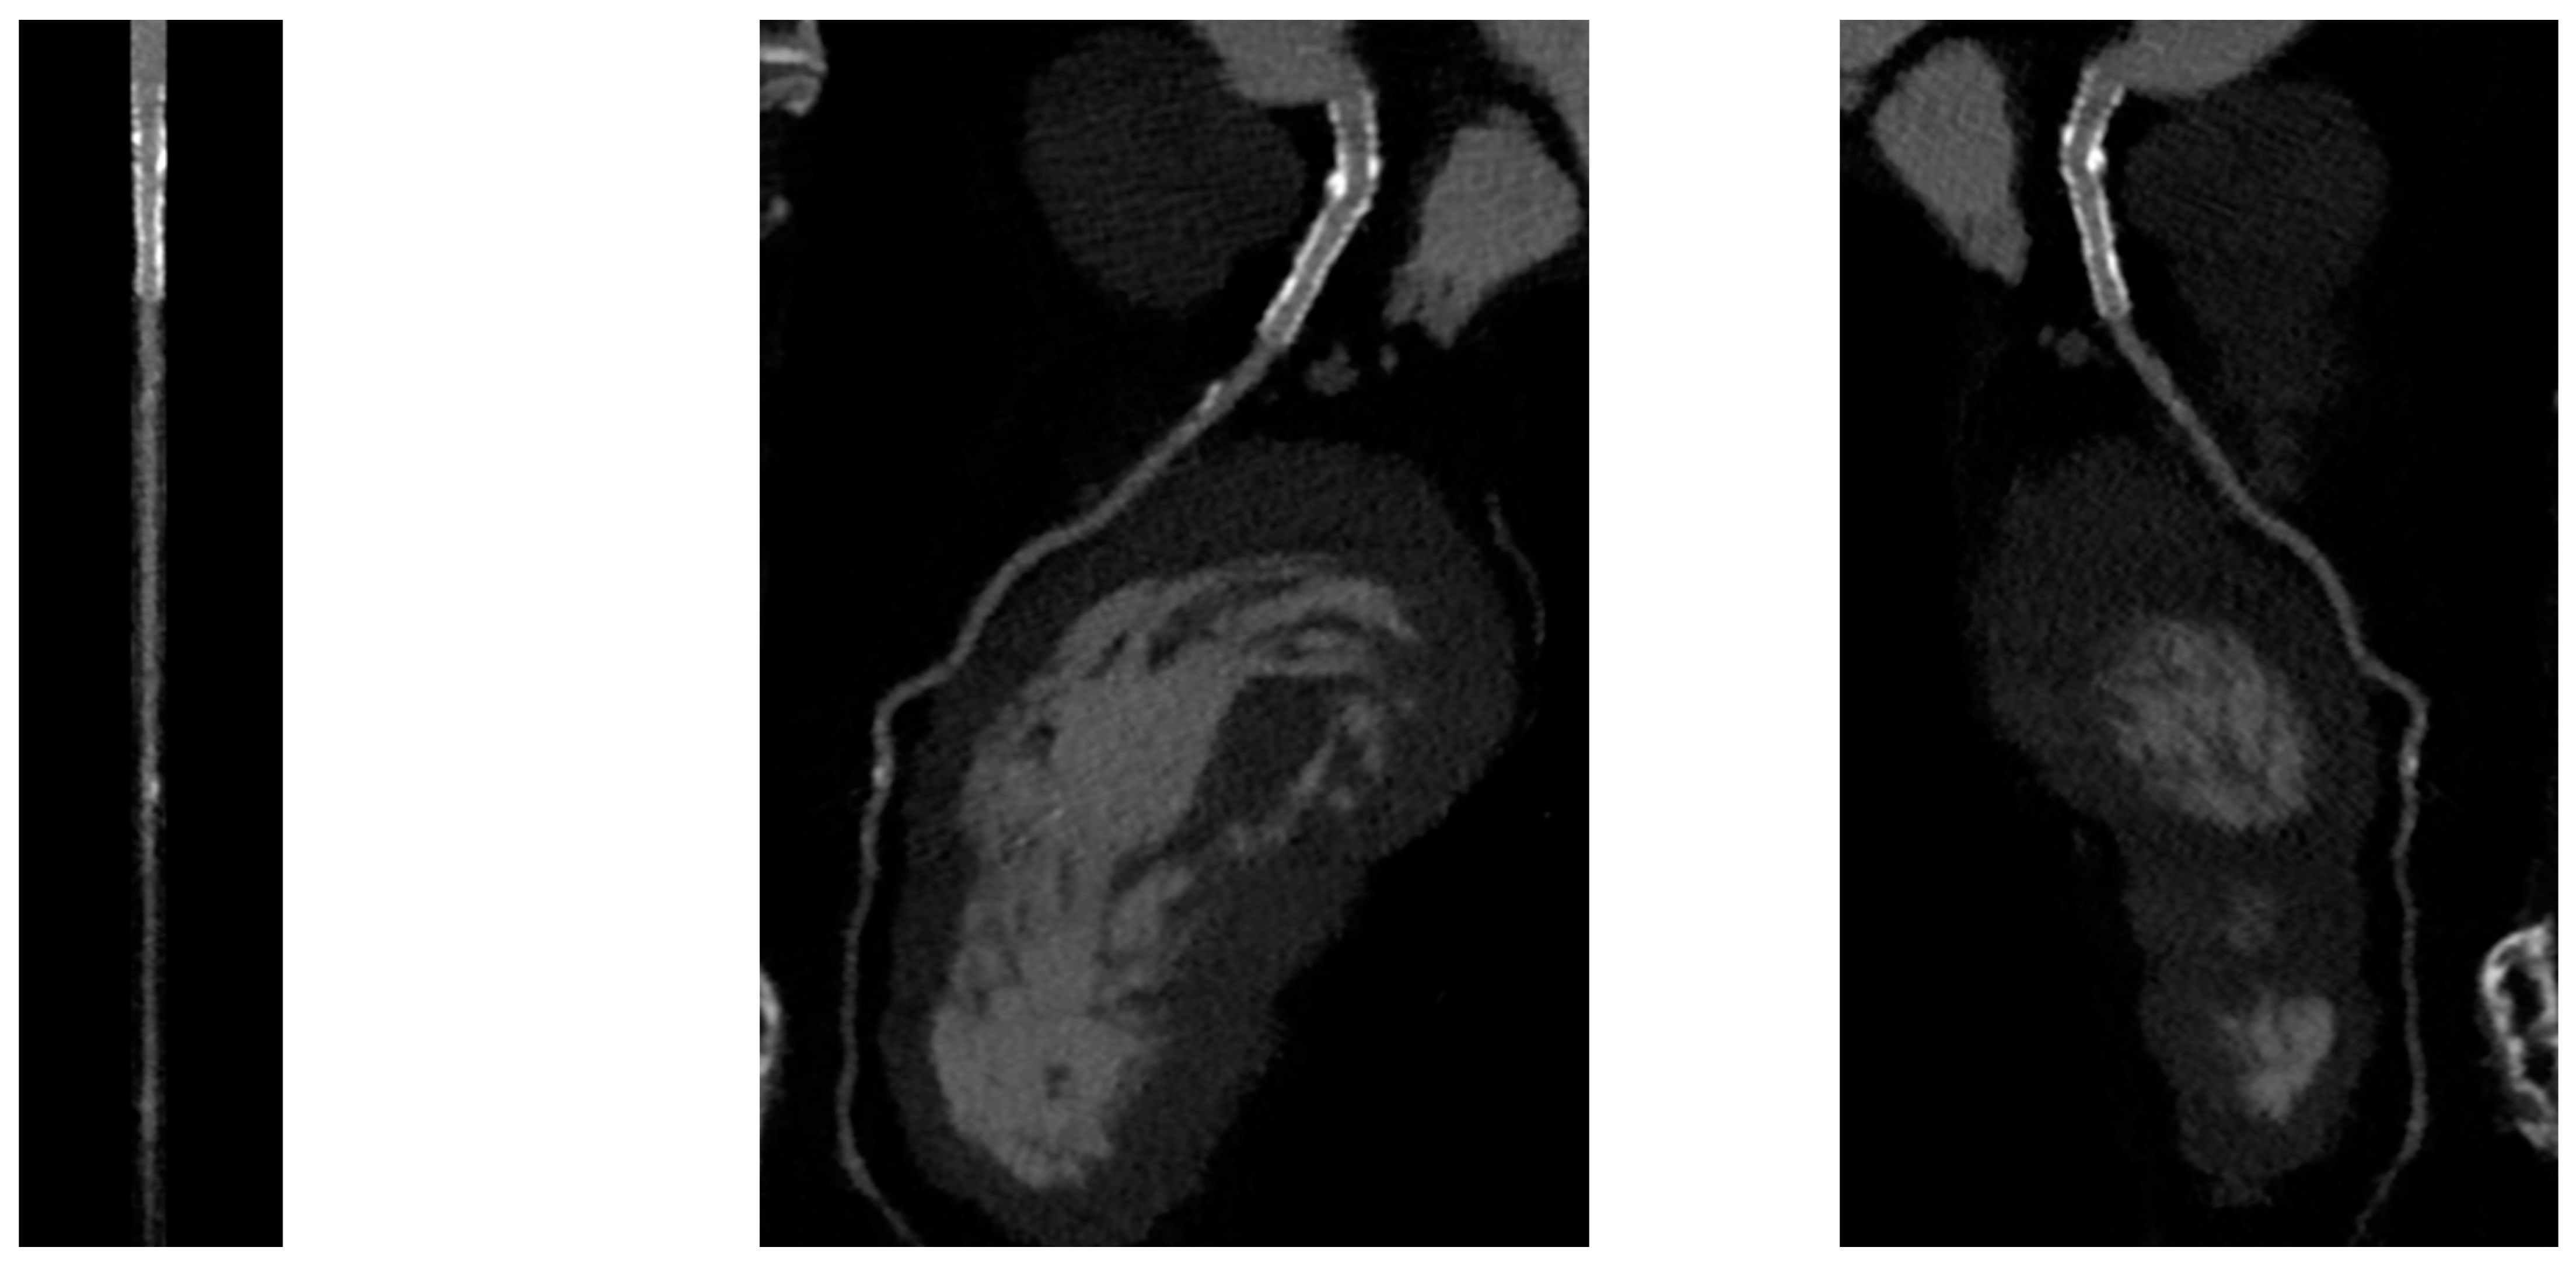

PCI of the left main (LM) improves survival, and in most cases, it is not inferior to surgical revascularization [14]. Intra-stent restenosis (ISR) is a complication of paramount importance, especially in the setting of LM revascularization, because of its relationship to adverse events. With current stents, ISR is due to neo-atherogenesis, which leads to a higher risk of destabilization and stent thrombosis. In the setting of LM, ISR at 15-month follow-up has been revealed to be present in up to 16% of total subjects, requiring invasive revascularization in 7% of cases. Coronary angiography represents the best technique for ISR assessment [14]. Planned Angiography Control (PAC) has been proposed to diagnose and treat ISR promptly, but its benefit remains to be established. An increased rate of percutaneous coronary interventions (PCI) without a reduction in cardiovascular events has been mainly reported. Some technical issues about the use of CCTA in coronary stent imaging have been described, such as the blooming effect, partial volume effect, motion artifacts, and inadequate intravascular contrast enhancement. The blooming effect is the most important issue, corresponding to a phenomenon in which stent struts appear thicker, causing an underestimation of stent lumen. However, with new technology development, CCTA provides a precise, noninvasive reconstruction of the coronary tree and may offer an alternative to invasive coronary angiography [15]. Figure 1 shows three multiplanar reconstructions of LM and left anterior descending with a drug-eluting stent previously implanted: struts of the stent appear clearly detectable, the stent seems to be well-positioned, and regarding stent lumen, it can be noted that there is good opacification and no evidence of ISR. Medium and distal tracts of the left anterior descending seem to be free from plaque proliferation and/or stenosis. Figure 2, instead, shows an ISR of a stent implanted in the proximal segment of the left circumflex coronary artery. Therefore, Figure 1 and Figure 2 demonstrate the feasibility of LM and proximal segment stent assessment by CCTA. Its use in the PAC setting has been investigated and may provide relevant advantages as it is a noninvasive examination. There are three different methods to determine the degree of ISR with CCTA: qualitative, semi-quantitative, and quantitative. The first technique provides that significant ISR (reduction of luminal diameter >50%) is visually detected: ISR is identified as a hypodense layer between the struts and the lumen. The second method is characterized by a four-point scale where 1 corresponds to the patency of the stent and 4 results in stent occlusion. Finally, the third technique provides that the percentage of stenosis is calculated as the ratio between diameters in the short axis of the narrowest stent lumen and of the proximal and distal reference segments [15]. Roura G et al. evaluated the agreement between CCTA and intravascular ultrasound (IVUS) to assess in-stent lumen diameters and lumen area of LM stents: the study highlighted a good agreement between the two techniques so that CCTA can be considered to analyze LM ISR [4]. A study by Van Mieghem CAG et al. assessed the performance of CCTA in the analysis of LM stenting: they enrolled 74 patients scheduled for follow-up coronary angiography after LM stenting, and they performed CCTA before coronary angiography. The study demonstrated that the accuracy of CCTA for detecting LM ISR was 98%; in particular, diagnostic accuracy was 98% both for patients with stented LM and with distal LM bifurcation lesions and only one side branch treated [5]. In subjects with complex bifurcation stenting (i.e., LM and both major side branches), the reliability of CCTA was 83%. The low number of false-positive scans leading to unnecessary diagnostic coronary angiograms should be acceptable, taking into account the potentially serious consequences of LM ISR [5]. Furthermore, the study underlined that the evaluation of stent diameter and area by CCTA had a good correlation with IVUS assessment. One of the most important issues arising from this study was the high radiation dose required for the analysis of stents by CCTA. However, as previously reported, new scanner developments (i.e., dual-source CT scanners) reduced patient dose.

Figure 1.

CCTA assessment of left main drug-eluting stent (Lumen image on the left, multiplanar reconstruction in the center and on the right). With a new CT scan, beam-hardening artifacts are reduced, and the stent lumen can be assessed with good performance.

Figure 2.

ISR in a stent previously implanted in the proximal segment of the left circumflex artery.